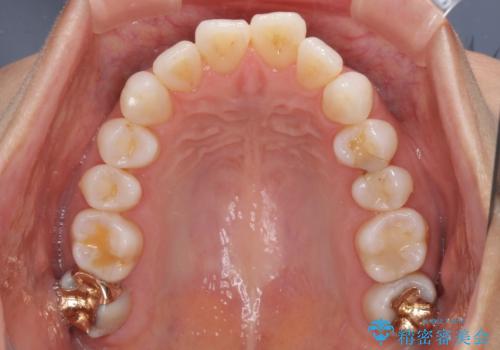

- 少しだけ前に飛び出ている前歯を気にして来院された患者様です。

上顎歯列全体を後方に移動させる必要があり、インビザライン単体での治療は困難と判断し、補助装置により左右側方歯列を移動させた後にインビザラインを用いることとしました。